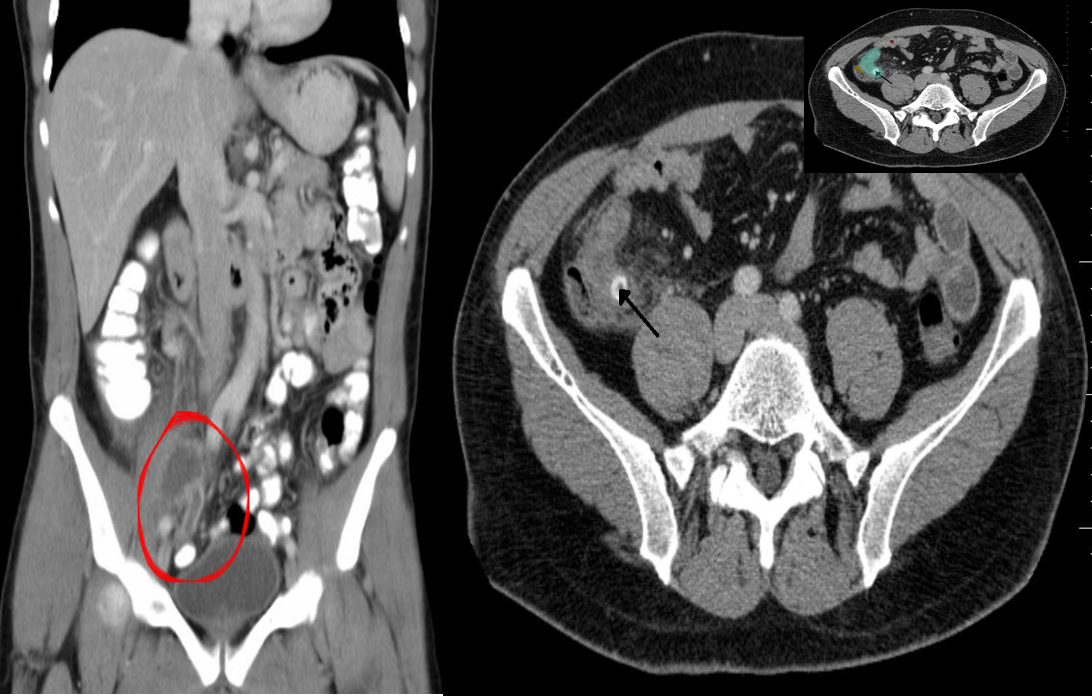

Abdomen CT (IV and oral contrast; coronal section)

The appendix is markedly distended, with a well-defined hyper-dense rim is visible at the cecal end of the appendix (peri-appendiceal abscess)

(B) Perforated appendicitis due to fecalith CT abdomen (IV contrast; axial section) There is distension of the appendix (green overlay). A well-defined, round, hyperdense lesion (black arrow), characteristic of an appendiceal fecalith. A small pocket of extraluminal air (red overlay)